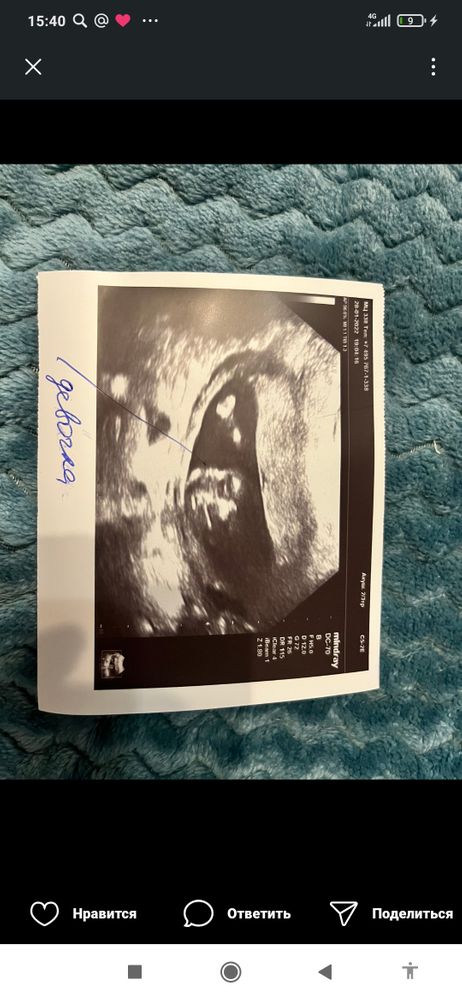

Я вот с девушкой переписывалась, у неё вот такое фото, сказали мальчик. Через неделю переделала, сказали девочка 100% Изображение

07.04.2022

И дали вот такое Изображение

Елена, да, здесь прямо видно и мошонку и сам пенис, во всяком случае очень похоже на фото

Aleksandra, это девочка

Это мошонка